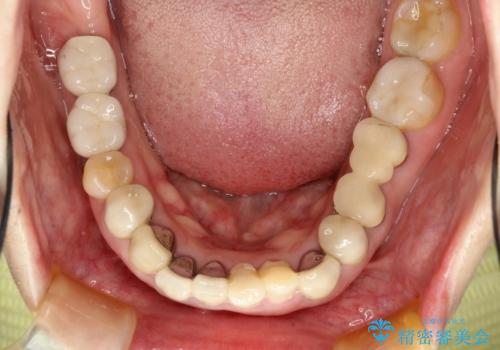

- 下顎の前歯に激痛を覚えて来院された患者様です。

取り急ぎ下顎前歯数歯の根管治療を、銀座しらゆり歯科医院長の林先生にお願いし、それ以外に気になっている、不自然な色調のクラウン、金属部分が見えてブラッシングがしにくいインプラント補綴、口元の突出感、出血のしやすい歯周ポケットなど、全てを解決するための治療を行うこととしました。